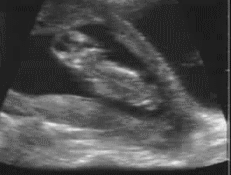

其實胎寶寶在孕期8周時,雖然沒有完全成型,但是長出的小小胚芽就已經有波紋狀的抽動了。到10周小手小腳已經幾乎長齊了,會出現飄動、浮動、跳動的動作。如果你在12周的時候去做NT(B超檢查),就已經可以在B超視訊中清晰的看到胎寶寶在打挺、游泳、翻身、吃手指了呢!

胎寶寶在媽媽肚子裡,就好比小魚在水裡,靈活的很。大動作翻身,打挺之類的,小動作吃手指,皺眉頭都有。一起來看看下面這張圖,看看胎寶寶都在做些什麼運動吧。